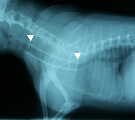

受診時。気管虚脱に対し気管内挿管の緊急処置が施されていた。 第1病日胸部X線写真。気管チューブを抜くと胸郭前口部で気管陰影消失(三角マーク間)。 引き続き、気管切開してシリコン製Tチューブを設置し気道確保した(マークはチューブ端を示す)。 第79病日、自己拡張型金属ステントに入れ替え、気管開存性と気道違和感が著明に改善した。

経過:町田夜間動物病院からの引継ぎで生命危機に関わる重度な気管虚脱であることが予想できたので、即座に慎重な治療計画を立てる必要性があった。気管内チューブ下では、違和感はあったが、room air吸入下でSpo2は97%を示し、肺機能は保てていた。Tチューブによる気道確保まで行う予定で万全の準備を整え、気管チューブを一度抜いた。予期していたとおり、ただちに呼吸困難とチアノーゼが生じた。すばやくビデオ透視と胸部X線撮影を実施し、ただちに麻酔導入し再挿管した。まず、将来的に自己拡張型金属ステント(Expandable metaric stent, EMS)を設置する可能性を考慮し、食道内にsizingカテーテルを挿入し気道内圧を20cmH2Oに保ち気管を拡張させX線撮影を行った。その後、気管支鏡検査にて、気管虚脱の範囲を同定し、また気管分岐部以降の虚脱がないことを確認した。Tチューブ設置のための気切部位は、X線所見と気管支鏡所見で同定した気管虚脱範囲の中点にあたる第5頚椎の部位とした。外径は輪状軟骨部の気管径の90%程度になるものを選び、8mmに決定した。気切孔から中枢側に大部分摺りこませ、口腔側へはガイドワイヤーを用い牽引して確実に引き寄せTチューブを設置した。設置後翌日より呼吸状態は改善し、食欲や一般状態もただちに回復した。術後管理は、1日2回のネブライゼーション(抗生剤、エピネフリン、生理食塩水、ステロイド)、Tチューブの気切部の栓を抜いて貯留痰の除去・吸引、1日2回の抗生剤の注射で行ったが、経過良好のため術後8日目に退院とした。自宅管理は、喀痰培養の結果に応じて抗生剤の処方を変えていったが、やはり入院時同様に1日2回のネブライゼーション、痰の除去、抗生剤の内服を継続した。Tチューブで管理中に、アメリカのEMSメーカーに気管sizingを含めた胸部X線写真の評価を依頼し、外径12mmX長さ52mmのステントを使用するよう指示された。ステント入手まで約1ヶ月程度を要した。しかしその間、軽度の咳がみられたがTチューブにて気管虚脱を十分よくコントロールできた。結局、オーナーと当院の都合が合い、犬の状態のよいときに(第79病日)、EMSへの交換を安全に無理なく行うことができた。EMS設置後、さらに状態は改善し、術翌日に非常に強く大きな声で吠えるになり、Tチューブ設置時より俊敏に動きまわるようになり、術後4日目に退院となった。第92病日、咳は消失した。